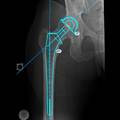

- 全髋关节置换手术中植入的假体多为生产商制造的标准化产品,由于受产品规格限制,使得假体与患者骨的匹配程度较低,术后易出现双下肢不等长的现象,不同程度影响了患者的术后生活质量。假体的松动是全髋关节置换手术术后另一个主要的并发症,也是导致假体关节脱位、返修的主要原因。这除了假体与患者骨的匹配程度较低有关外,还与另外两个因素有关,一是术中临床医师大多数凭着自己的经验决定植入假体的位置和深度以及切除坏死股骨颈的高度,导致假体与股骨有效髓腔的契合度降低,出现术后双肢不等长,假体下沉等现象;二是植入假体后力的传入途径发生了根本的变化,关节应力直接通过假体传到髋关节,而不同于生理关节的应力通过骨小梁从髋关节传到髋关节,造成应力遮挡,使得骨组织被吸收而萎缩,减低其承载能力,改变应力集中点,病人出现术后剧烈疼痛等现象。上述问题的理想化的解决方案,一是 “量体裁衣”、设计、制造在形态学、生物力学、材料力学等方面能最佳适应个体髋关节解剖特点的个体化、定做式人工髋关节;二是实际手术前虚拟、演练植入过程、精确预知植入后的效果。 多排螺旋CT和较高磁场MR等现代医学成像设备对疾病的解剖显示日益精细。计算机技术及现代医学成像技术的显著进步为运用反求工程技术原理及计算机虚拟现实技术应用于术前手术虚拟、植入假体设计制造等提供了现实途径。 本课题运用反求工程技术原理,采用薄层CT扫描数据计算机辅助重建活体髋关节三维CAD模型;基于Billing等定义及立体解析几何原理,计算机辅助、精准、半自动化地分别测量股骨头直径、容积及中心位置、颈干角、髋臼前倾及外展角度、髋臼窝半径等重要解剖参数;应用计算机虚拟现实技术、计算机逼近拟合算法及有限元力学分析等工具,虚拟理想化假体模型,研究其形态学;虚拟假体植入,比较活体髋关节重建模型及假体植入后的力学分布曲线,为人工髋关节置换术前三维可视化、优化手术方案以及研制适合国人体质、高契合度及最佳力学曲线分布的定制髋关节假体等提供技术探讨、实体模型和设计依据。 为此,本组研究分别从以下五个方面展开: (1)探讨一种精准、简便的股骨颈前倾角测量方法及其临床应用及其临床应用;推导出股骨颈前倾角公式,采用公式法计算右侧前倾角为17.3251°±1.1345°,传统法测量16.853°±7.631°; (2)基于以上方法和测量过程,系统测量左右侧髋臼前倾角等解剖学参数,为人工髋关节置换手术及个性化定制假体设计提供解剖学基础并初步探讨临床应用软件设计与开发; (3)髋关节三维可视化和形态学研究。采用髋关节螺旋CT数据,半自动分割髋臼窝、股骨头、股骨颈及股骨干,体素重建的方法对髋关节及股骨同时进行三维重建,从不同的角度观察髋关节三维立体及其周围重要结果毗邻关系,并在模型上进行三维解剖学测量,探讨其临床应用;为髋关节手术治疗、微创外科、立体定向、导航系统及虚拟假体设计提供三维可视化模型; (4)构建正常成年人股骨三维有限元模型。模型导入ANSYS 10.0软件后进行体网格划分,并再导入Materialise软件进行模型材料属性赋值,在ABAQUS软件定义边界条件,模拟直接暴力作用股骨干横界面生物力学研究,垂直水平面加载500N载荷,观察载荷后关节及股骨的应力曲线分布,提示股骨干以其内侧中下1/3交界处的应力最大,应力值分别为29.0Mpa,从而为假体材料和植入后的研究提供有限元力学分析基础。 (5)模拟具有理想形态学的人工髋关节植入。根据所测得的相关参数,设计理想形态学的假体模型,导入3D功能模块,虚拟三度空间精确调整假体植入体中的位置。在计算机中成功的实现个性定制假体等手术,并可预见和评估手术的结果,从而制定出最优的手术方案。患者所需假体和髋臼杯的型号将以报告的形式输出,为提高手术成功率及延长假体植入的寿命提供了一条新的、精确合理的途径。

- 目的:为研制适合国人体质、高契合度及最佳力学曲线分布的定制髋关节假体及优化手术方案等提供技术探讨、实体模型和设计依据。方法:1.反求工程技术原理计算机重构30例健康成人在体髋关节三维模型; 2.根据Billing定义及解析几何学原理推导出以定义的关键点坐标值为自变量的股骨颈前倾角计算公式,自动计算前倾角等参数; 3.计算机辅助拟合髋臼窝、股骨头、股骨上段髓腔等形态; 4.虚拟假体植入,分离骨皮质和髓腔,虚拟生理不同受力情境,有限元力学分析软件分析其力线分布; 5.根据上述结果筛选形态学、力学分布最优化假体,优化手术方案; 结果:1.推导出股骨颈前倾角公式,测量重要形态学参数; 2.重建出了髋关节三维可视化模型并可任意、实时旋转观察; 3.股骨三维有限元模型以内侧中下1/3交界处的应力最大,应力值为29.0MPa; 4.计算机虚拟实现个性定制假体等手术,并可预见和评估手术的结果、最优化手术方案。患者所需假体和髋臼杯的型号以文本报告的形式输出。 结论:上述公式、三维有限元模型及假体设计、虚拟植入等可应用于定制理想髋关节假体设计及优化手术方案。